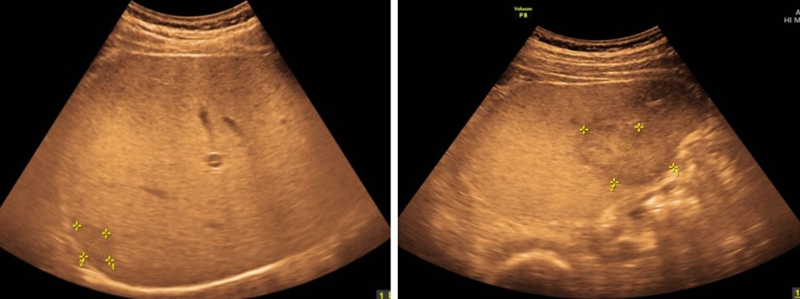

Hình ảnh siêu âm phát hiện khối u gan hạ phân thùy V-VI, VII

Siêu âm ổ bụng phát hiện hình ảnh khối u gan hạ phân thùy V-VI, VII, gan nhiễm mỡ, theo dõi bệnh lý nhu mô gan mạn tính, polyp túi mật.

Trên kết quả siêu âm và HCC wako, bệnh nhân được chẩn đoán sơ bộ là u gan hạ phân thùy V-VI, VII chưa loại trừ HCC, gan nhiễm mỡ độ 1, polyp túi mật, nang thận phải, đái tháo đường type 2, viêm gan B mạn.